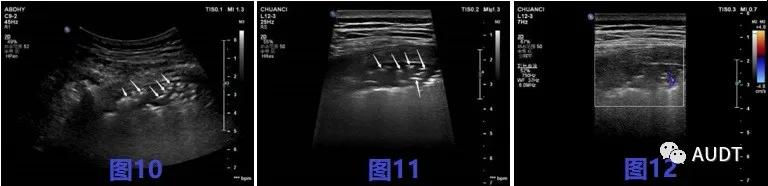

进展后期,图8-9 CT扫描显示双肺呈大片样,条带样实变影,图10-12超声显示相应肺周胸膜局限性增厚。实变病灶内超声可见粗大支气管充气征,伴病灶后弥漫性B线,实变区域实变与正常肺组织交界区可见少量星点状血流信号。